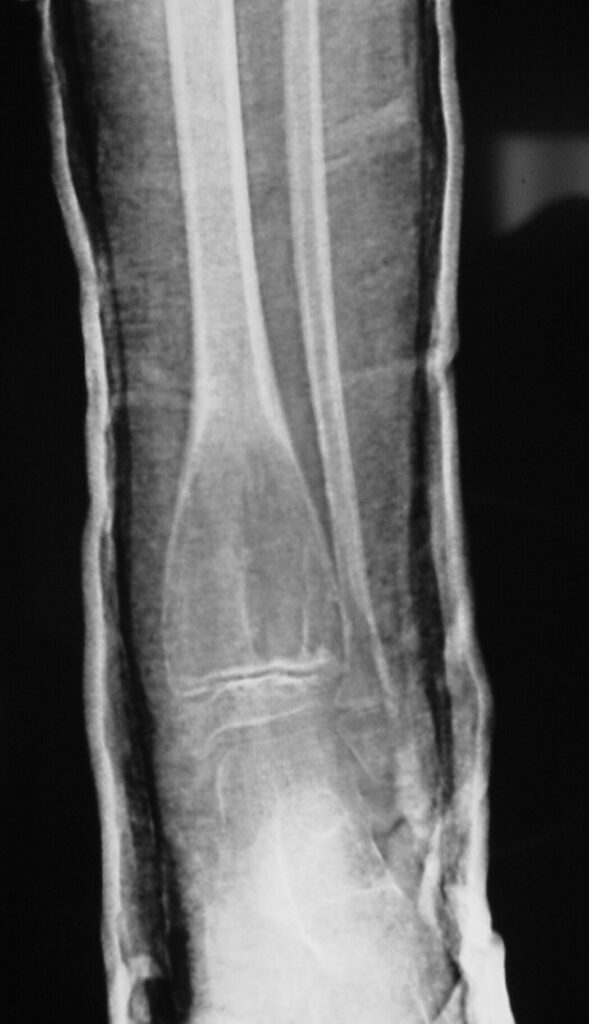

Plain x-ray

• Radiolucent

• Geographic and Eccentric lesion that is well circumscribed

• May scallop or expand the surrounding cortex

• Surrounded by sclerotic bone

• Methaphyseal region most common

• Eccentric

• Elevation of the periosteum could be seen as a benign appearing periosteal reaction (continuous periosteal reaction)

Fig 1a. Plain X-ray (AP View). ABC of the Distal Tibia: Geographic Well Circumscribed Lesion in the distal tibia. The cortices are expanded. There are internal septations. There is no internal mineralization. There is no evidence of a malignant appearing periosteal reaction such as a sunburst or hair on end pattern or codman’s triangle.

Fig 1b: Plain X-ray (Lateral View): ABC of Distal Tibia. Notice how the cortices or bony contour appears expanded. The tumor has been eroding the inner aspect of the cortex of the bone. In response the periosteum on the outside lays down new bone which gives the bone and expanded contour.